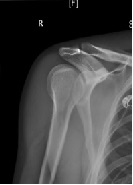

Case Report: Minimally Invasive Open Reduction and Internal Fixation of a Humeral Head-Splitting Fracture-Dislocation in A Young Man

Kyle Andrews1*, Ryan Sefcik2, Jacob Stirton1, Nabil Ebraheim1